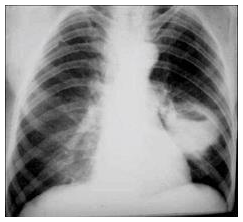

Um homem de 36 anos procura o pronto-socorro com queixa de febre baixa, tosse produtiva e perda de peso há 3 semanas. Trabalha na zona rural como cortador de cana, é tabagista e “bebe socialmente”. Tem epilepsia desde a infância e nos últimos 3 meses tem apresentado convulsões por ter abandonado o tratamento. A radiografia de tórax mostra: